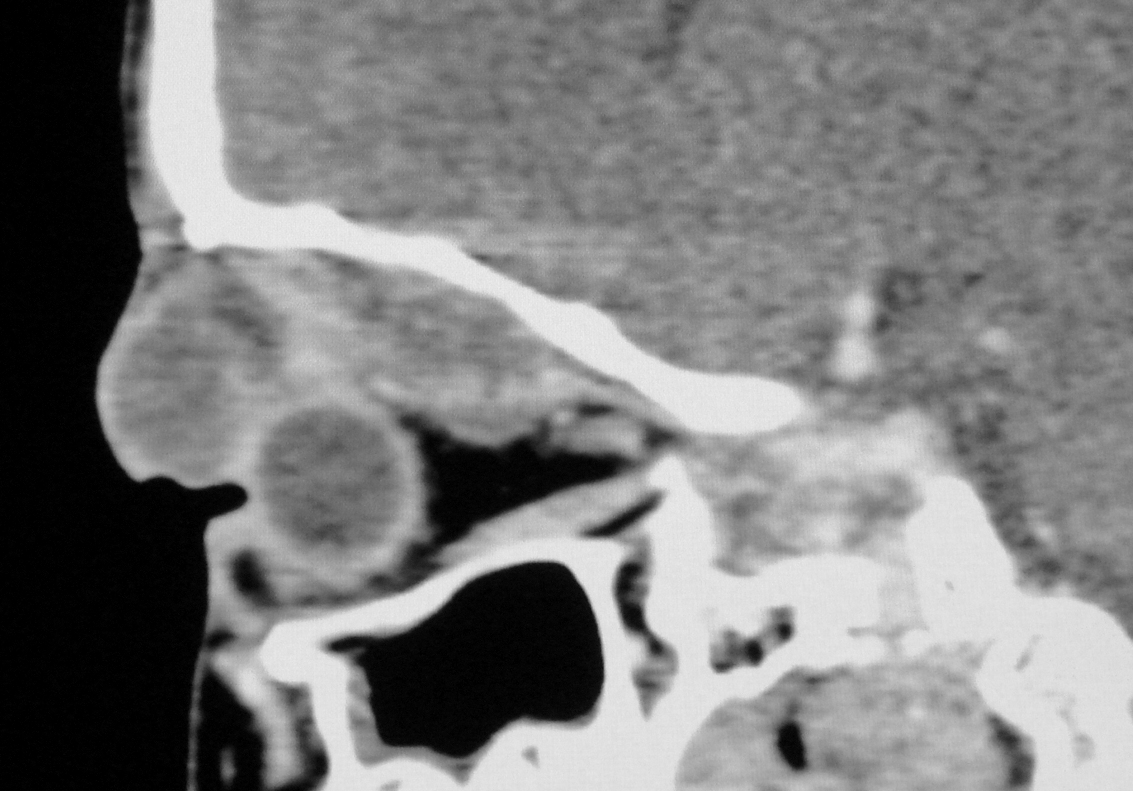

The ocular involvement of the cysticercosis is a rare entity involving eyelids, extraocular muscles, orbit, conjunctiva, anterior chamber, uvea, retina, vitreous and optic nerve. All the extraocular muscles are involved in myocysticercosis. Ultrasonography and Computed tomography are the imaging modalities for evaluation of ocular cysticercosis. The patients can be treated with systemic steroids and albendazole; however surgical excision is the treatment of choice. We report a rare case of extraocular myocysticercosis in nine years old boy diagnosed on ultrasonography and computed tomography.